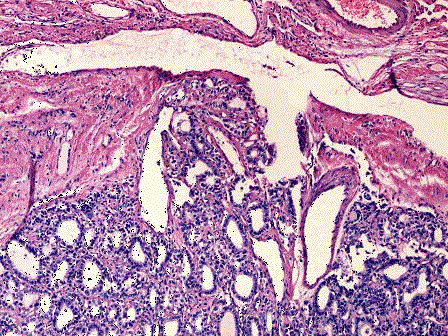

问题 如图为甲状腺腺瘤镜下观和甲状腺高分化滤泡癌镜下观,仔细比较,二者最重要的区别是 ( )

选项 A.是否具有完整包膜 B.高分化滤泡癌的滤泡结构和上皮细胞形态异型性明显 C.肿瘤包膜、血管受侵犯和发生转移才能确诊为癌 D.核分裂象的多少是诊断标准 E.患者年龄的大小是决定因素

答案 C